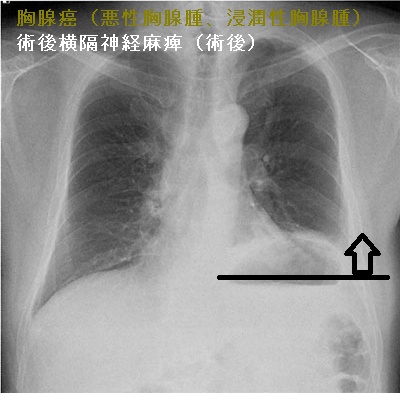

胸腺癌(悪性胸腺腫、浸潤性胸腺腫)は前胸部から肺門部まで浸潤し、横隔神経自体にも浸潤するため、摘出手術で横隔神経を損傷する可能性が高い(術後横隔神経麻痺)。術後横隔神経麻痺では、術後から息が深く吸えなくなります。内肋間筋・補助呼吸筋と代償性の呼吸数増加で補える場合が多いが、重症例は胸腔鏡下横隔膜縫縮術の適応。

術後横隔神経麻痺は、特に浸潤性の強い甲状腺癌、前縦隔に浸潤する甲状腺癌(甲状腺未分化癌 甲状腺原発扁平上皮癌 など)の切除手術後にも起こります。